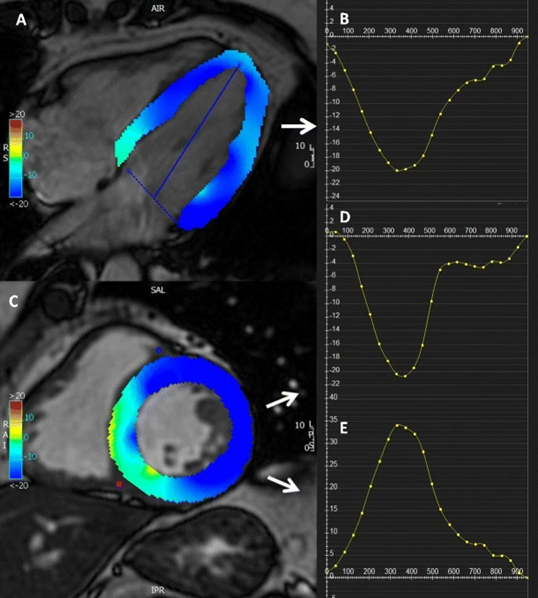

There are different methods of measuring cardiac strain, out of which cine steady-state free precession (SSFP) MRI is the most commonly used method (Figure 9). It is considered the gold standard for heart imaging and thus is routinely used in clinical imaging. However, it does not contain direct information about the cardiac strain, and thus, there is a need for a better strain estimate method from SSFP MRI [10]

4.4. Results

The results of PINN prediction are shown in Figure 11. On the left is the ground truth image, in the middle is the PINN prediction without the Fourier transform, and on the right is the PINN prediction with the Fourier transform. The prediction with the Fourier transform has much better boundary differentiation because the higher frequencies included in the input allow the neural network to better capture the sharp changes in the deformation field at the boundaries, which are difficult to represent with low-frequency components alone.